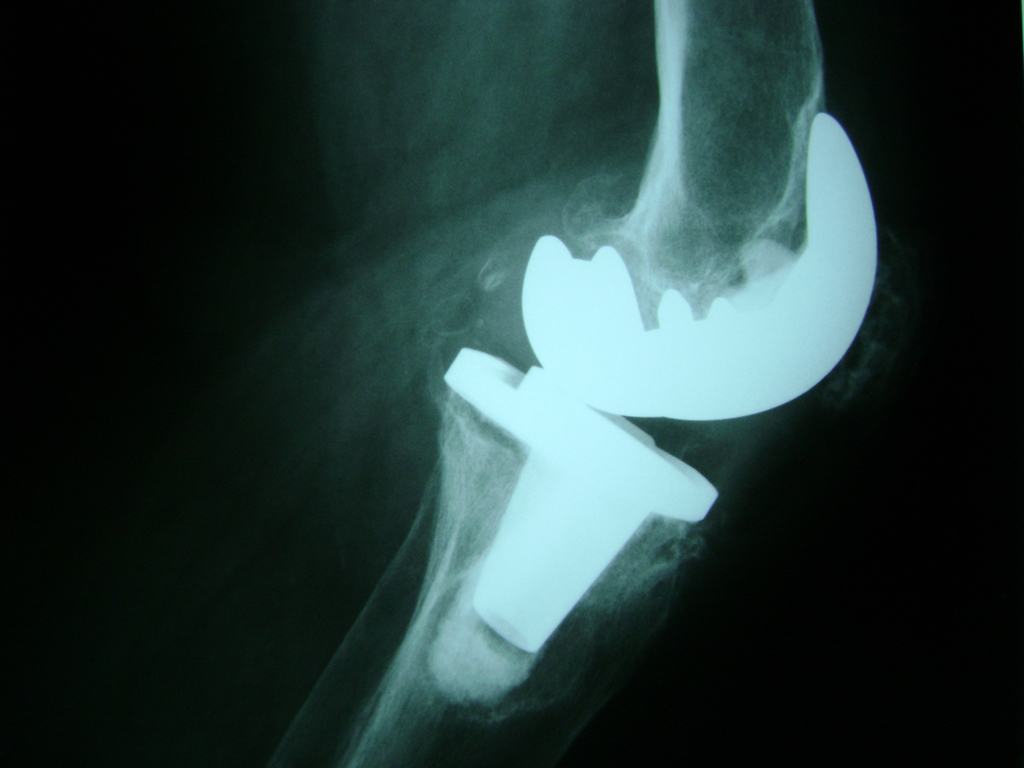

Cirugías de Húmero - Rodilla

La artroscopia de rodilla es un cirugía en el cual la estructura interna de la articulación es examinada ya sea para realizar un diagnostico o para realizar un tratamiento, este procedimiento se realiza utilizando un instrumento parecido a un pequeño tubo llamado artroscopio.